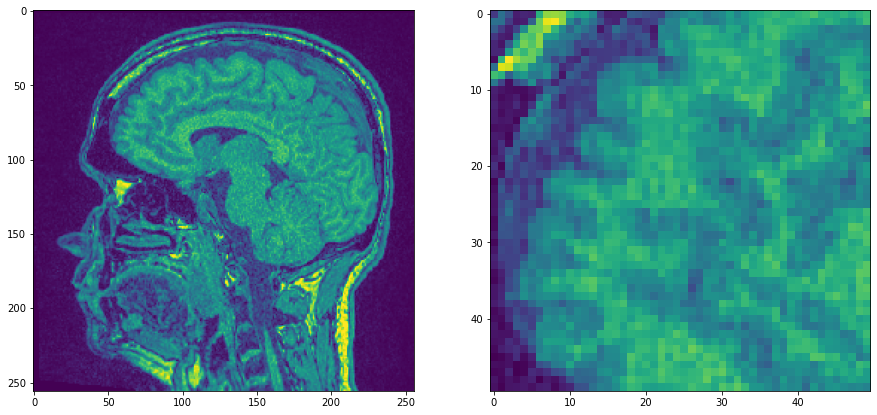

Nous commençons par un seul plan de l’ensemble de données MRT d’exemple qui est assez bruyant et nous faisons un zoom.

noisy_mri_zoom = noisy_mri[50:100, 50:100]

axs[0].imshow(noisy_mri)

axs[1].imshow(noisy_mri_zoom)